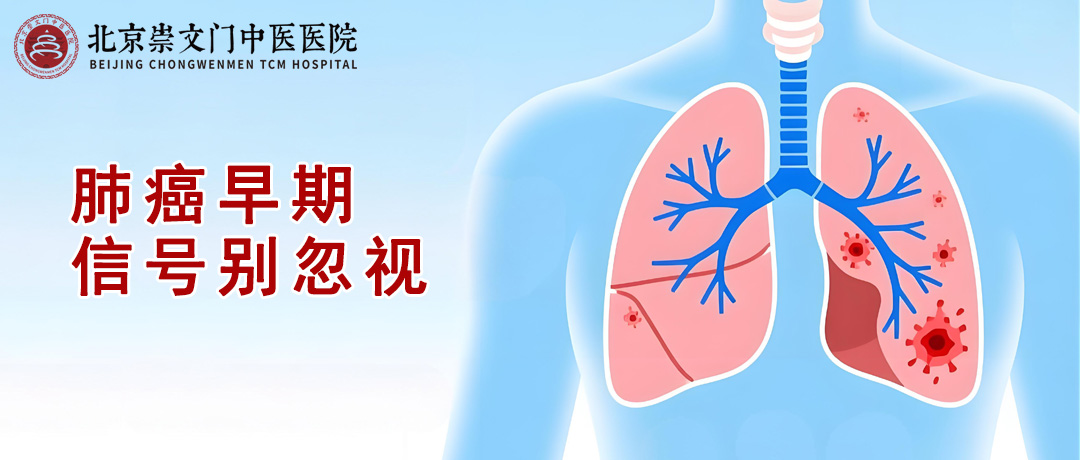

发表于:2025-12-14肺癌是威胁健康的“头号杀手”之一,但很多人不知道,早期肺癌可能通过身体发出的...